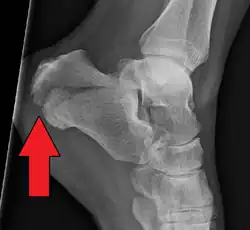

Conventional radiography is usually the initial assessment tool when a calcaneal fracture is suspected. Recommended x-ray views are (a) axial, (b) anteroposterior, (c) oblique and (d) views with dorsiflexion and internal rotation of the foot. However, conventional radiography is limited for visualization of calcaneal anatomy, especially at the subtalar joint. A CT scan is currently the imaging study of choice for evaluating calcaneal injury and has substituted conventional radiography in the classification of calcaneal fractures.[13] Axial and coronal views are obtained for proper visualization of the calcaneus, subtalar, calcaneocuboid and talonavicular joints.